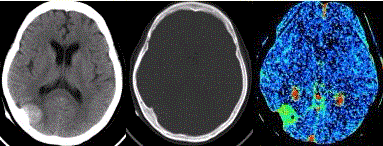

问题 患者女,60岁,头痛半月余。既往体健。腰椎穿刺检查提示脑脊液压力增高。CT及CT灌注表现如下图。 关于该肿瘤,描述正确的是

选项 A.恶性多见 B.病变常与颅骨关系不大 C.好发于中年男性 D.以颈外动脉供血为主 E.不发生于脑室内

答案 D